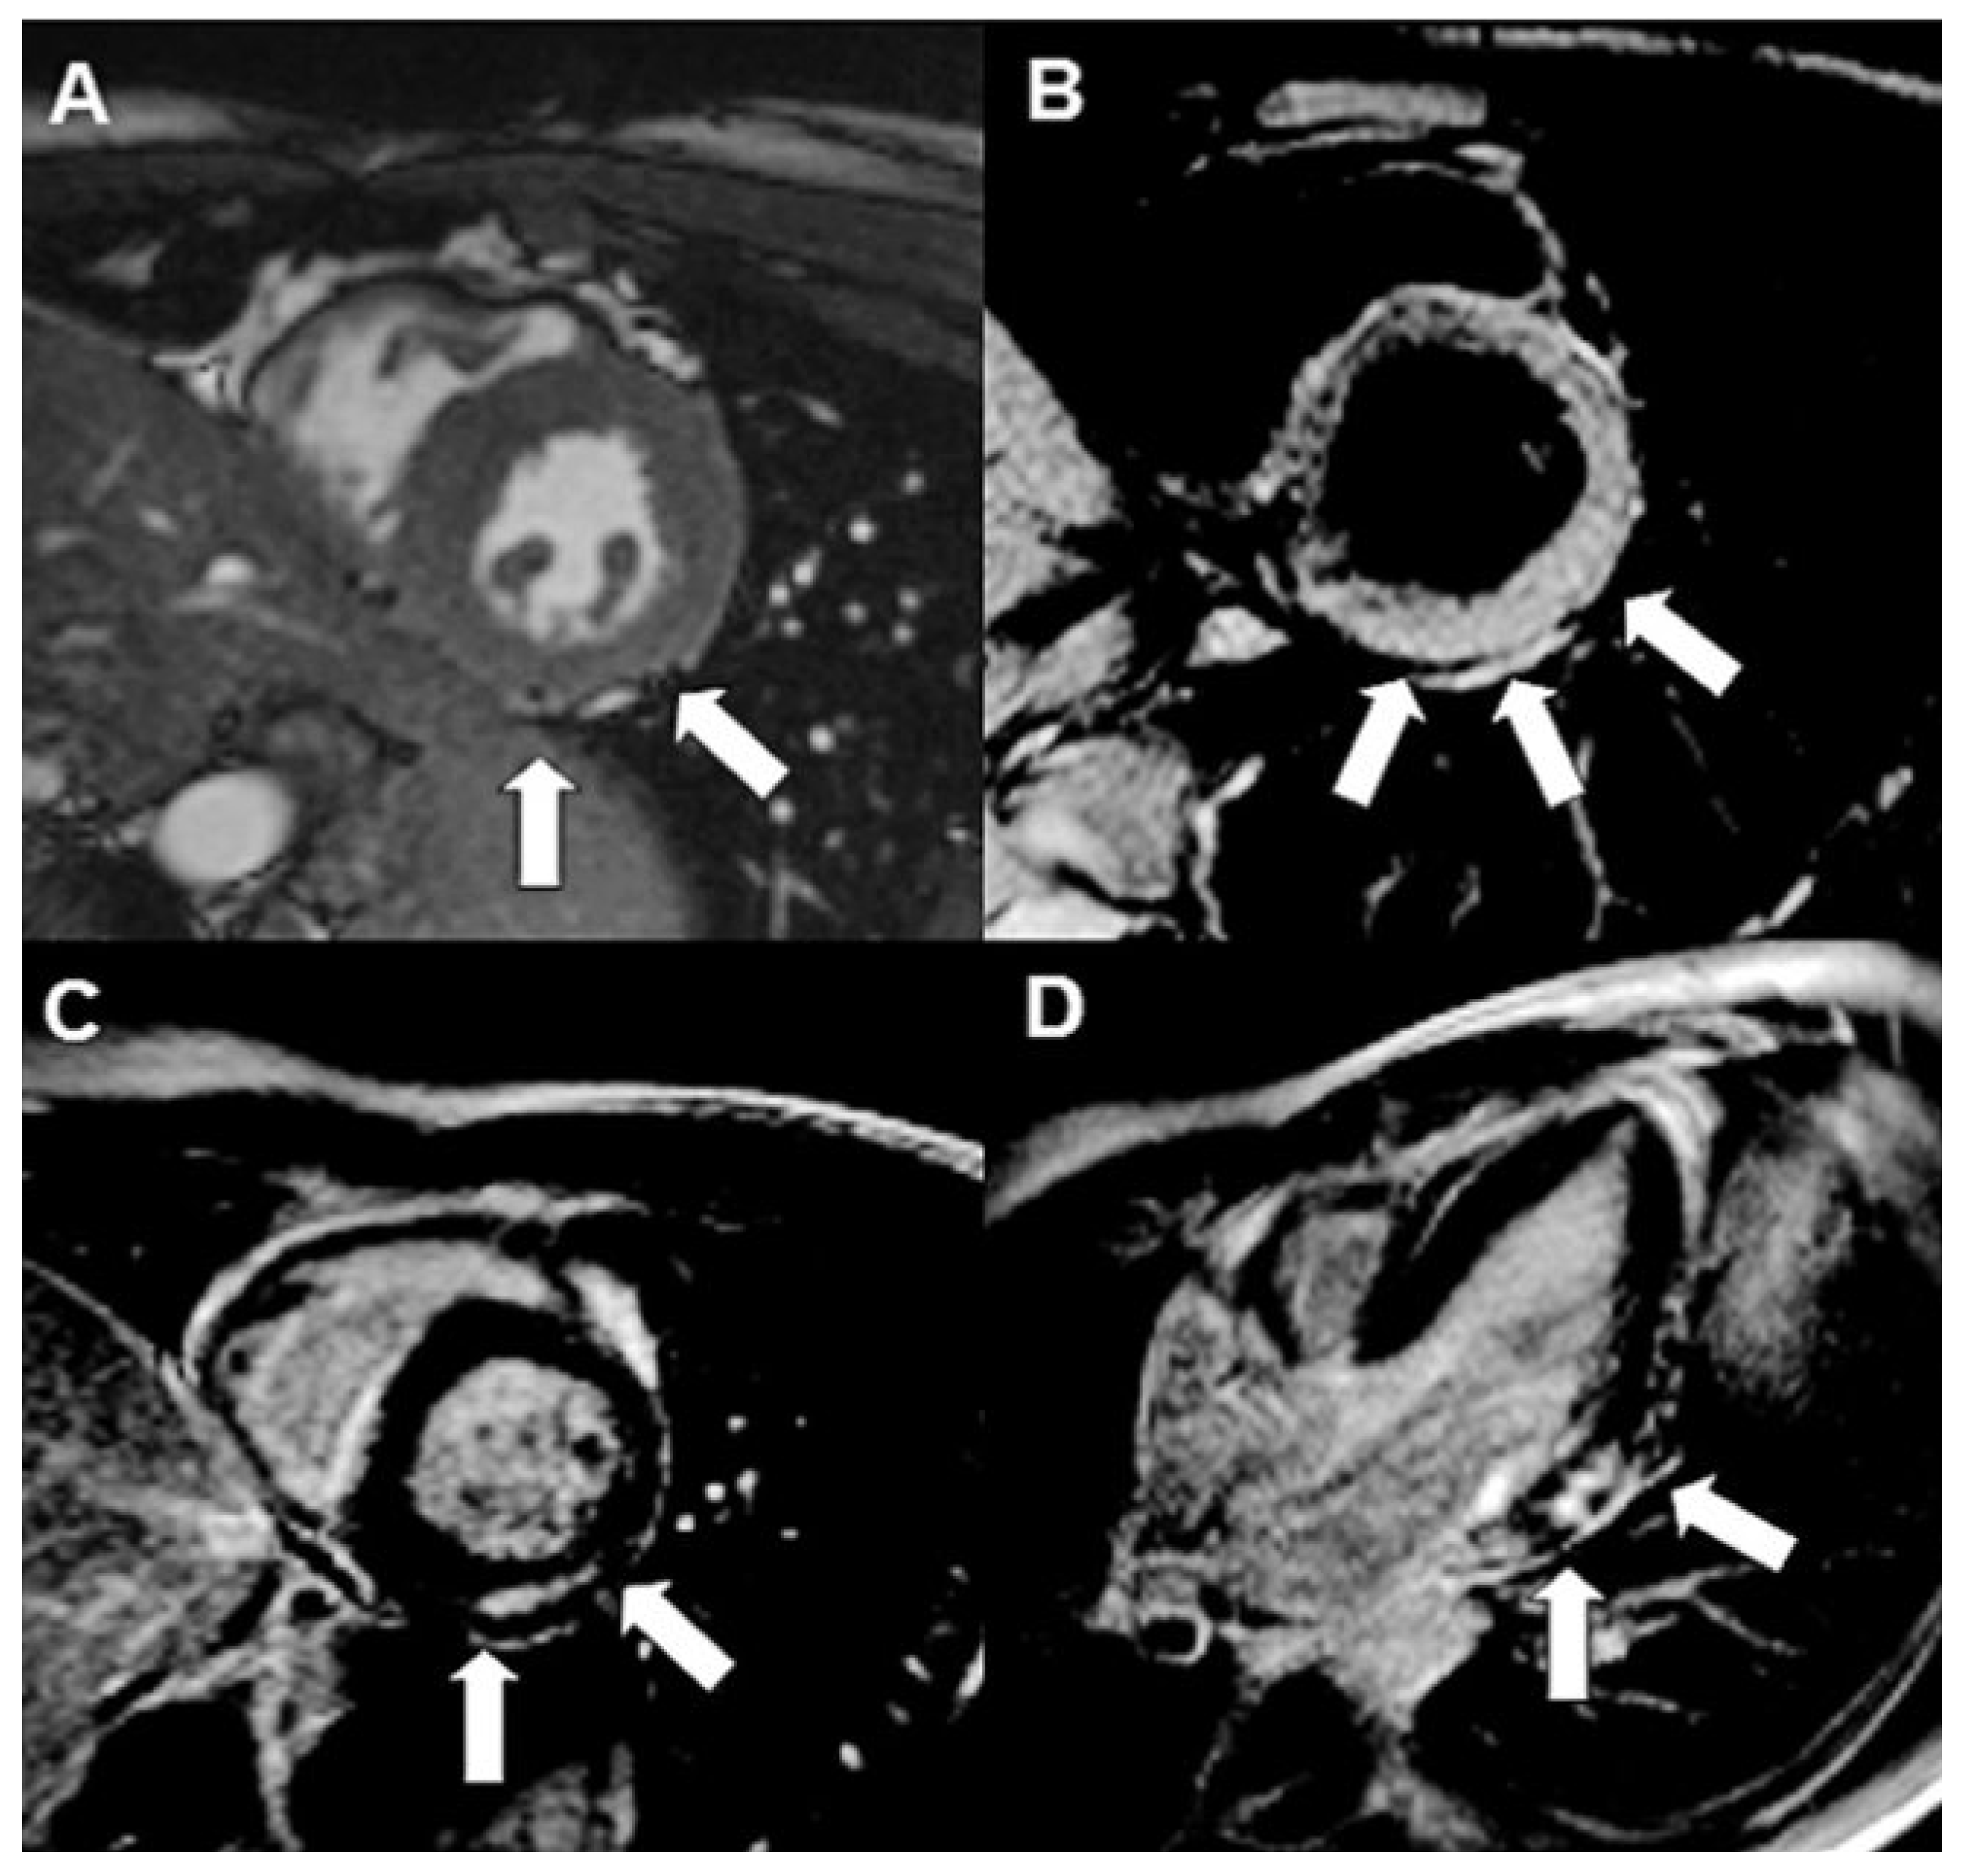

Evaluation of Acute Peri-Myocarditis with Cardiac Magnetic Resonance Imaging

Case report